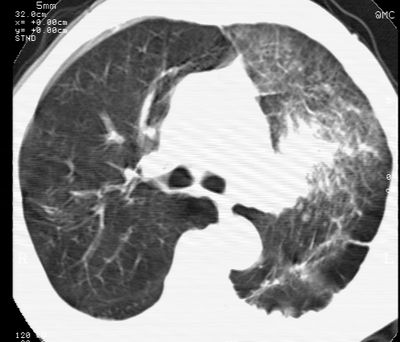

标题: CT24000:M65,胸痛,胸闷月余,既往慢支,肺气肿,肺心病 [打印本页]

标题: CT24000:M65,胸痛,胸闷月余,既往慢支,肺气肿,肺心病

左肺门肿块,相应支气管闭塞,左肺上叶、舌叶大片及散在高密度影,部分呈不张改变,两肺纹粗乱,左侧胸腔积液。考虑左侧中央型肺癌伴阻塞性改变。

左肺门见巨大软组织肿块影,直径约--,境界清,左上肺叶支气管变窄,左上肺舌叶见大片状密实影,余肺纹理增多、紊乱、纤细、部分网格状,两肺透亮度增高,纵隔内见增大多发淋巴结影,心影略左偏,左侧少量胸腔积液。

左侧中央型肺癌伴左上肺舌叶不张、纵隔淋巴结转移,左侧少量胸腔积液。